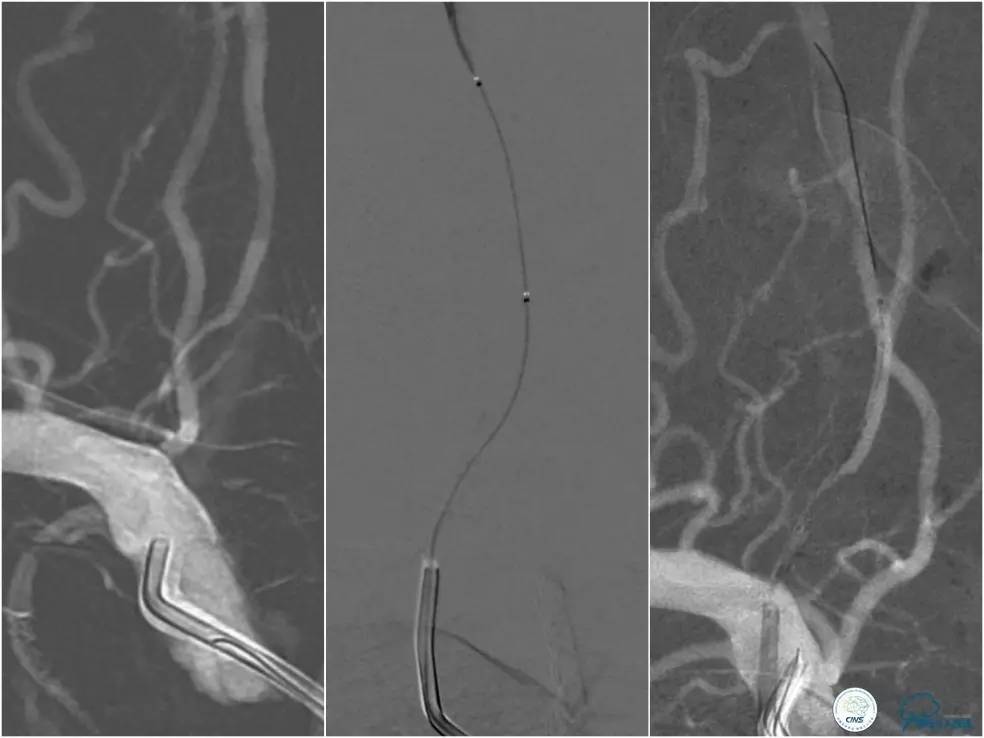

全麻下右侧股动脉穿刺置入8F动脉鞘,6F导引导管到位,送入Traxcess(0.014″200cm)微导丝+Echelon-10微导管小心通过右侧椎动脉V1段狭窄处至V2段远端,交换撤出Traxcess微导丝,送入Transend(0.014″300cm)微导丝至V2段远端(图10)。

图10

Ultra-Soft球囊(3.0mm×20mm)于狭窄处预扩张后置入EXCEL支架(4.0 mm× 24mm),球扩后造影见支架贴壁良好,远端血管显影好,前向血流TICI3级。6F导引导管沿微导丝通过右椎动脉V1段支架至V2段(图11)。